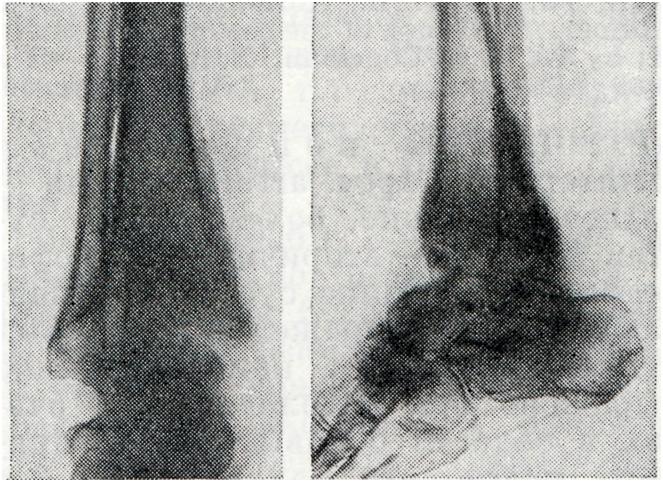

Артропатия нейрогеннаяАртропатия нейрогенная (arthropathia; греческое arthron сустав + pathos страдание, болезнь; синоним сустав Шарко) — вторичное дистрофическое заболевание суставов, развивающееся при поражении различных отделов центральной нервной ситемы; наиболее резко выражено при патологических очагах в области боковых рогов спинного мозга, его задних корешков и столбов, поражениях периферических нервов и гипоталамической области, обеспечивающих вазомоторно-трофическую иннервацию суставов. В происхождении артропатий нейрогенных основную роль играет потеря болевой чувствительности, расслабление связочного аппарата и мышц и обусловленная этим постоянная микротравматизация суставов, Артропатия нейрогенная наблюдается при сирингомиелии, спинной сухотке, диабетическом полиневрите. Кроме того, артропатии нейрогенные могут развиваться при нарушении мозгового кровообращения и некоторых других неврологических заболеваниях. Клиническая картина.При сирингомиелии артропатия встречается у 10—15% больных. Поражаются преимущественно локтевой и плечевой суставы, реже — суставы кисти (рис. 1), еще реже — другие. Это объясняется тем, что при сирингомиелии преимущественно поражается серое вещество спинного мозга на уровне шейных и верхних грудных сегментов»

У одних больных превалируют процессы гипертрофии, у других — атрофии костной, хрящевой и соединительной ткани. Суставные поверхности при этом деформируются. Появление внутрисуставного выпота, отечность мягких тканей и деформация внутрисуставных концов эпифизов приводят к увеличению размеров пораженного сустава. В мелких суставах кисти чаще наблюдаются явления деформирующего артроза, приводящего к искривлению пальцев. Несмотря на выраженность процесса, функция пораженного сустава нередко длительно сохраняется, а боли отсутствуют. Это объясняется тем, что при сирингомиелии снижается или полностью утрачивается болевая и температурная чувствительность. |